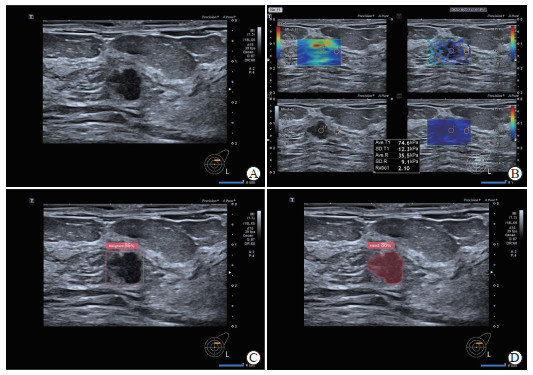

图  2   浸润性乳腺癌的超声AI辅助诊断与剪切波弹性成像分析

A 61-year-old female patient was pathologically confirmed with invasive breast cancer. A: Conventional ultrasound demonstrated a solid nodule at the 2 o'clock position of the left breast, with a clear boundary and an irregular shape; B: Shear wave elastography of the breast nodule showed a maximum elasticity value of 74.6 kPa; C: Ultrasound AI-assisted diagnosis system identified the breast nodule, with an 86% probability of malignancy; D: AI-assisted ultrasound diagnosis system identified the breast nodule and performed nodule filling. AI: Artificial intelligence.